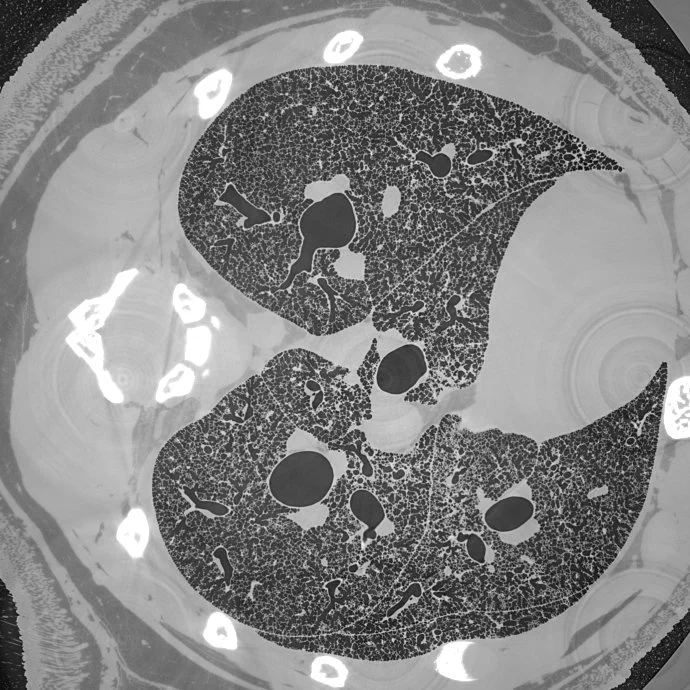

Micrometer-resolution X-ray tomographic full-volume reconstruction of an intact post-mortem juvenile rat lung

An international team of researchers, headed by the TOMCAT group and collaboration partners at the University of Bern, have used this method to acquire micrometer-scale resolution datasets on the entire lung structure of a juvenile rat in its fresh natural state within the animal’s body and without the need for any fixation, staining or other alteration that would affect the observed structure (Borisova et al, 2020, Histochem Cell Biol ). This openly accessible 1.2 TB dataset (http://link.springer.com/article/10.1007/s00418-020-01868-8(link is external)) reveals the smallest structural features of the lung, the alveoli, over the whole extent of the lung.